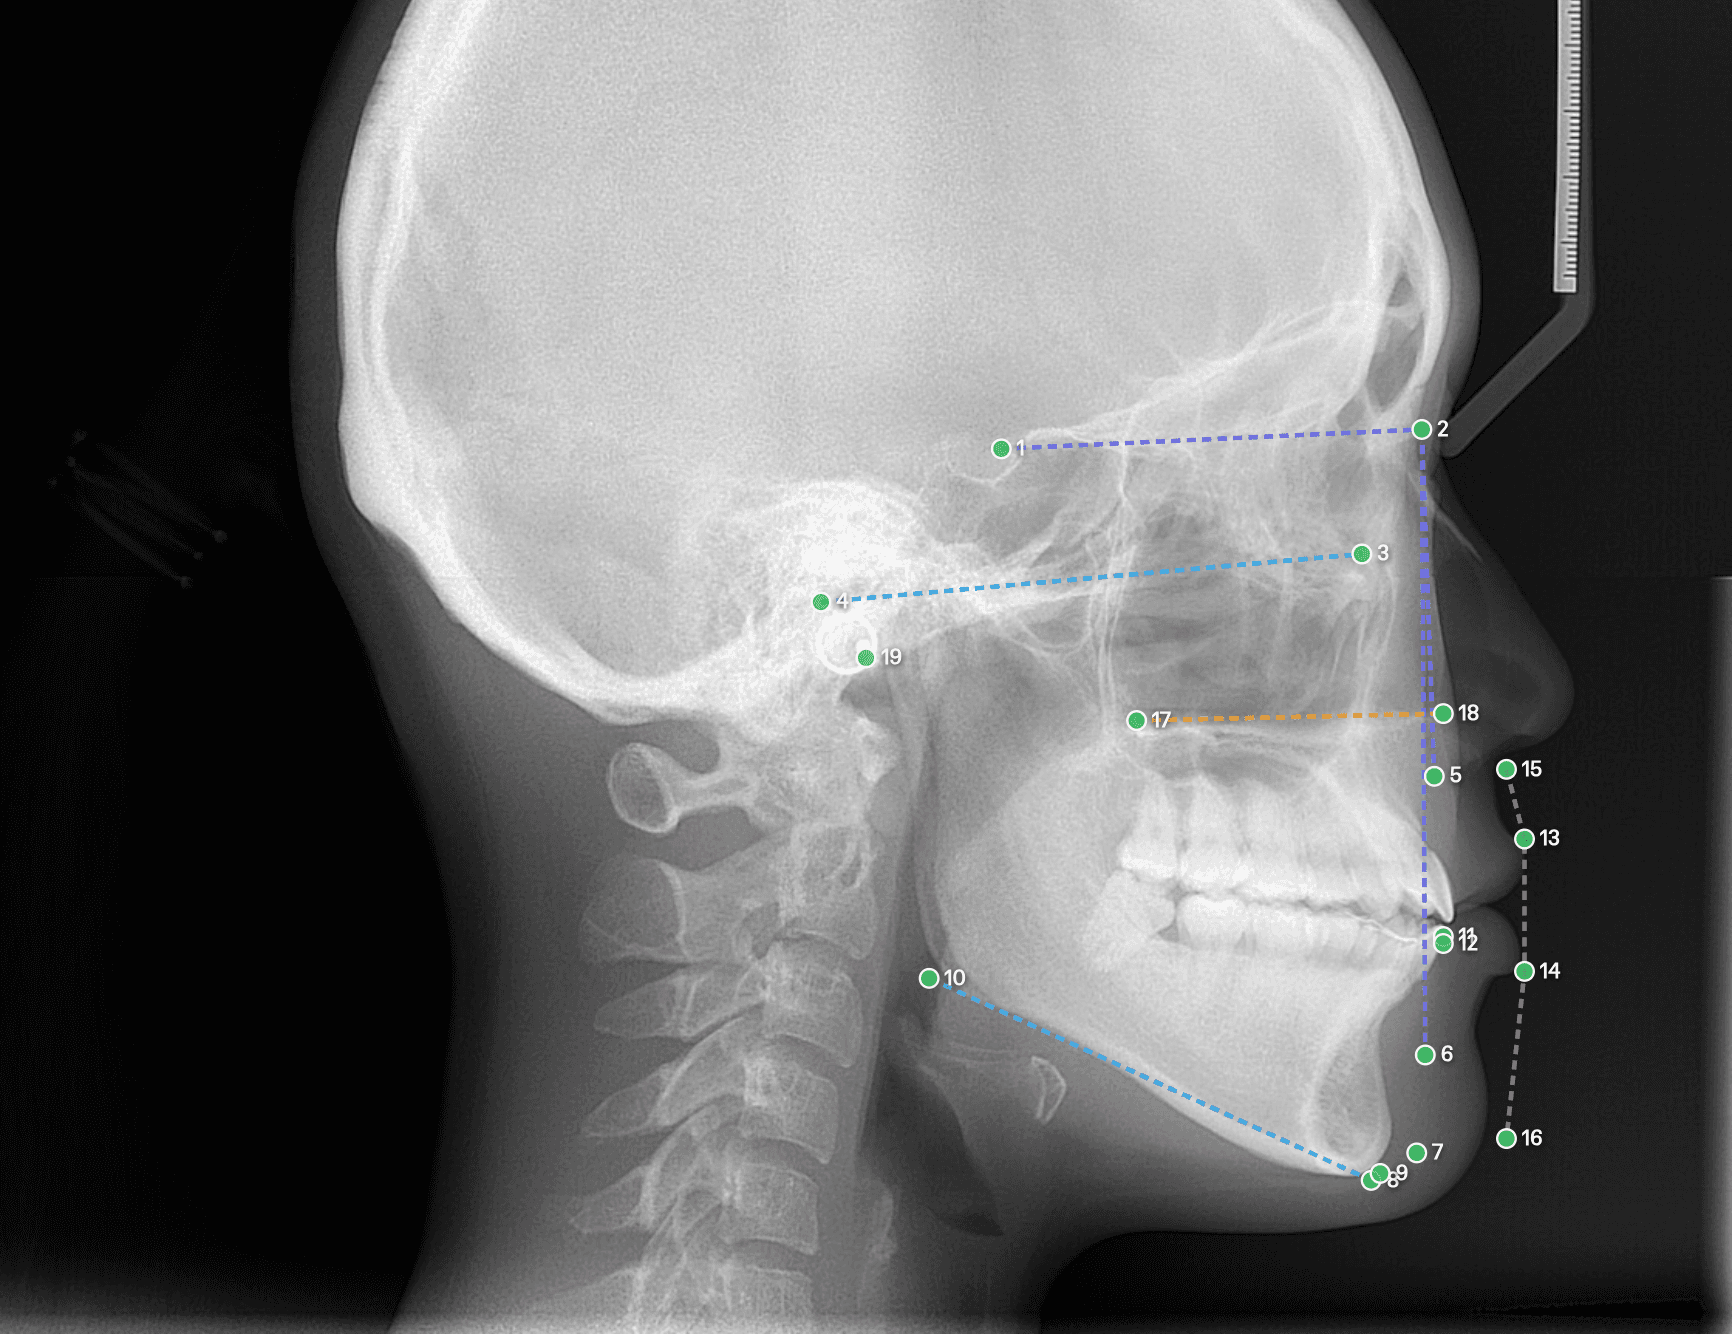

Céphalométrie automatisée

Idéal pour l'orthodontie. Le placement automatique des points céphalométriques et le calcul instantané des angles et mesures accélèrent drastiquement la préparation de vos traitements ODF.